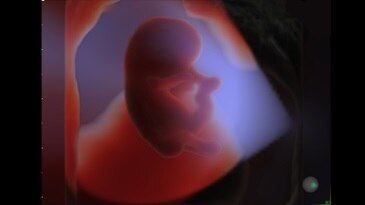

HD𝘭𝘪𝘷𝘦

Семейство технологий Voluson для глубинного понимания анатомии и дифференцировки структур в объеме с беспрецедентной реалистичностью.

Изображение HDlive™ плода, созданное с помощью SonoRenderlive

HDlive Studio on a 10-week fetus